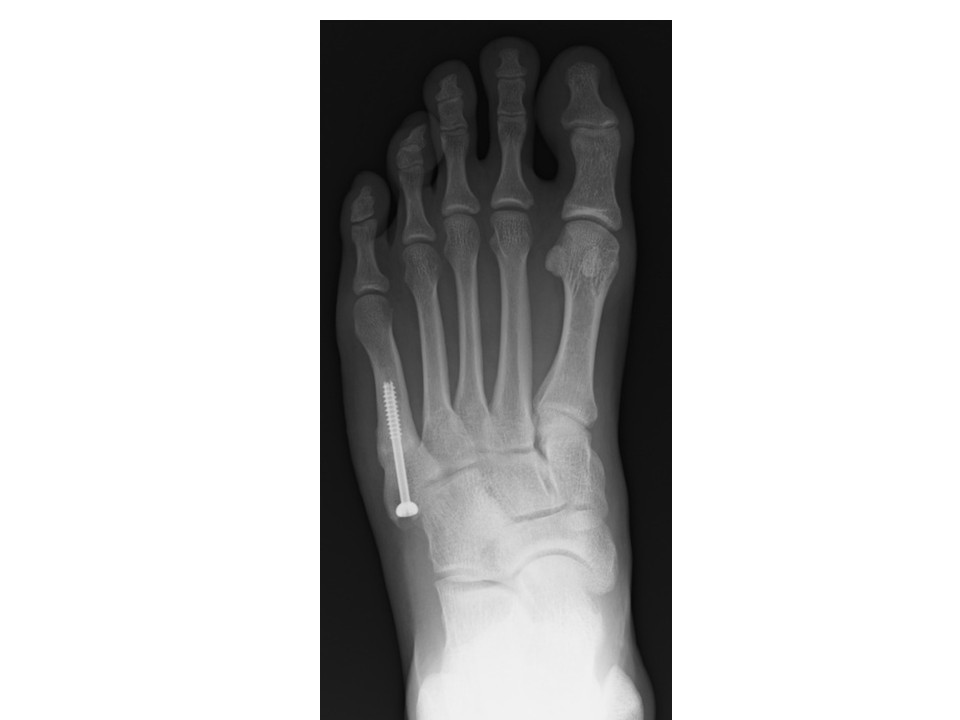

The syndesmosis bunionectomy — Bellevue Podiatric Physicians Screw Removal From 5Th Metatarsal I broke my right 5th metatarsal about 12 years ago. Surgical interventions and adjunctive therapy. Intramedullary screw fixation was the most common method of fixation. Any one of the five metatarsal bones in the foot might sustain a fracture. The collective findings regarding ims in proximal fifth metatarsal fractures (pfmf) indicate a 10% overall rate of metal removal,. The past. Screw Removal From 5Th Metatarsal.

Pre(a) and postoperative (b) radiographs of a fifth metatarsal base Screw Removal From 5Th Metatarsal I broke my right 5th metatarsal about 12 years ago. Detailed step by step desription of intramedullary screw or lag screw fixation for proximal extraarticular fractures of the 5th metatarsal (march fracture) located in our module on. Any one of the five metatarsal bones in the foot might sustain a fracture. Intramedullary screw fixation was the most common method of. Screw Removal From 5Th Metatarsal.